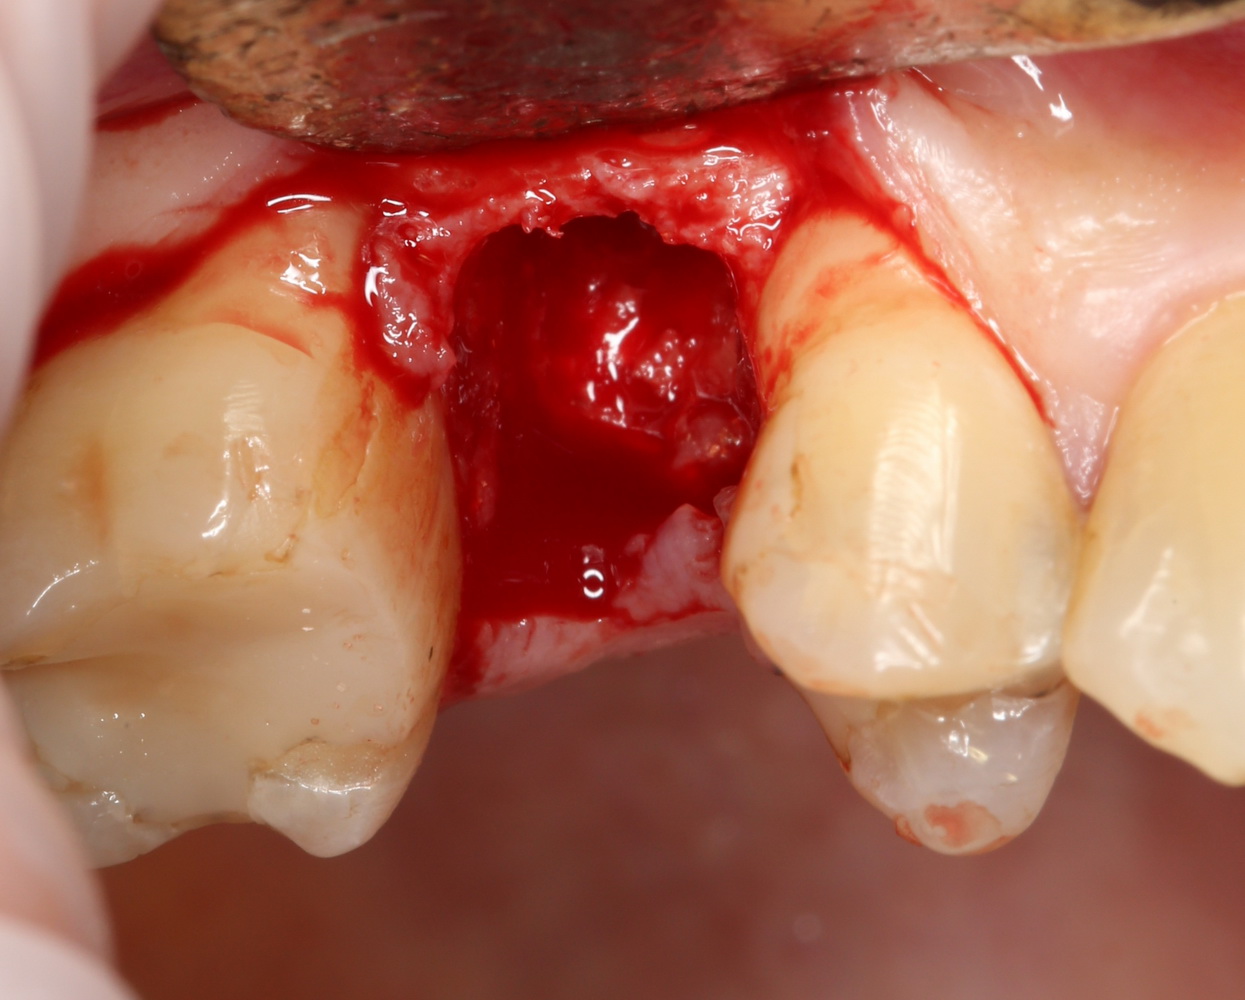

Что мы и сделали. Удалили зуб:

Критически важно провести удаление аккуратно, чтобы не разрушить и без того тонкие стенки альвеолы. Вообще, в хронометраже операции немедленной имплантации удаление зуба занимает 75% времени, это наиболее сложная и деликатная часть вмешательства.